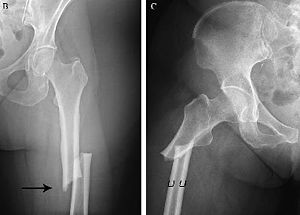

2. FRACTURAS POR INSUFICIENCIA Ó PATOLÓGICAS

1. factor fundamental es la debilidad ósea

1. Pueden

1. deberse a procesos con osteopenia u osteosclerosis

1. enfermedades óseas fragilizantes constitucionales ó metabólicas

1. procesos locales como tumores primarios o metastásicos, ó procedimientos iatrogénicos que debiliten los huesos

2. FRACTURAS POR FATIGA Ó ESTRÉS

1. resultado de solicitaciones mecánicas repetidas.